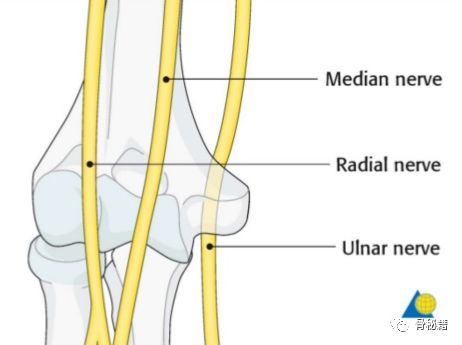

肱骨远端的三个神经也需要注意哦,尤其是后入路的时候,有时需要对桡神经和尺神经都进行显露。